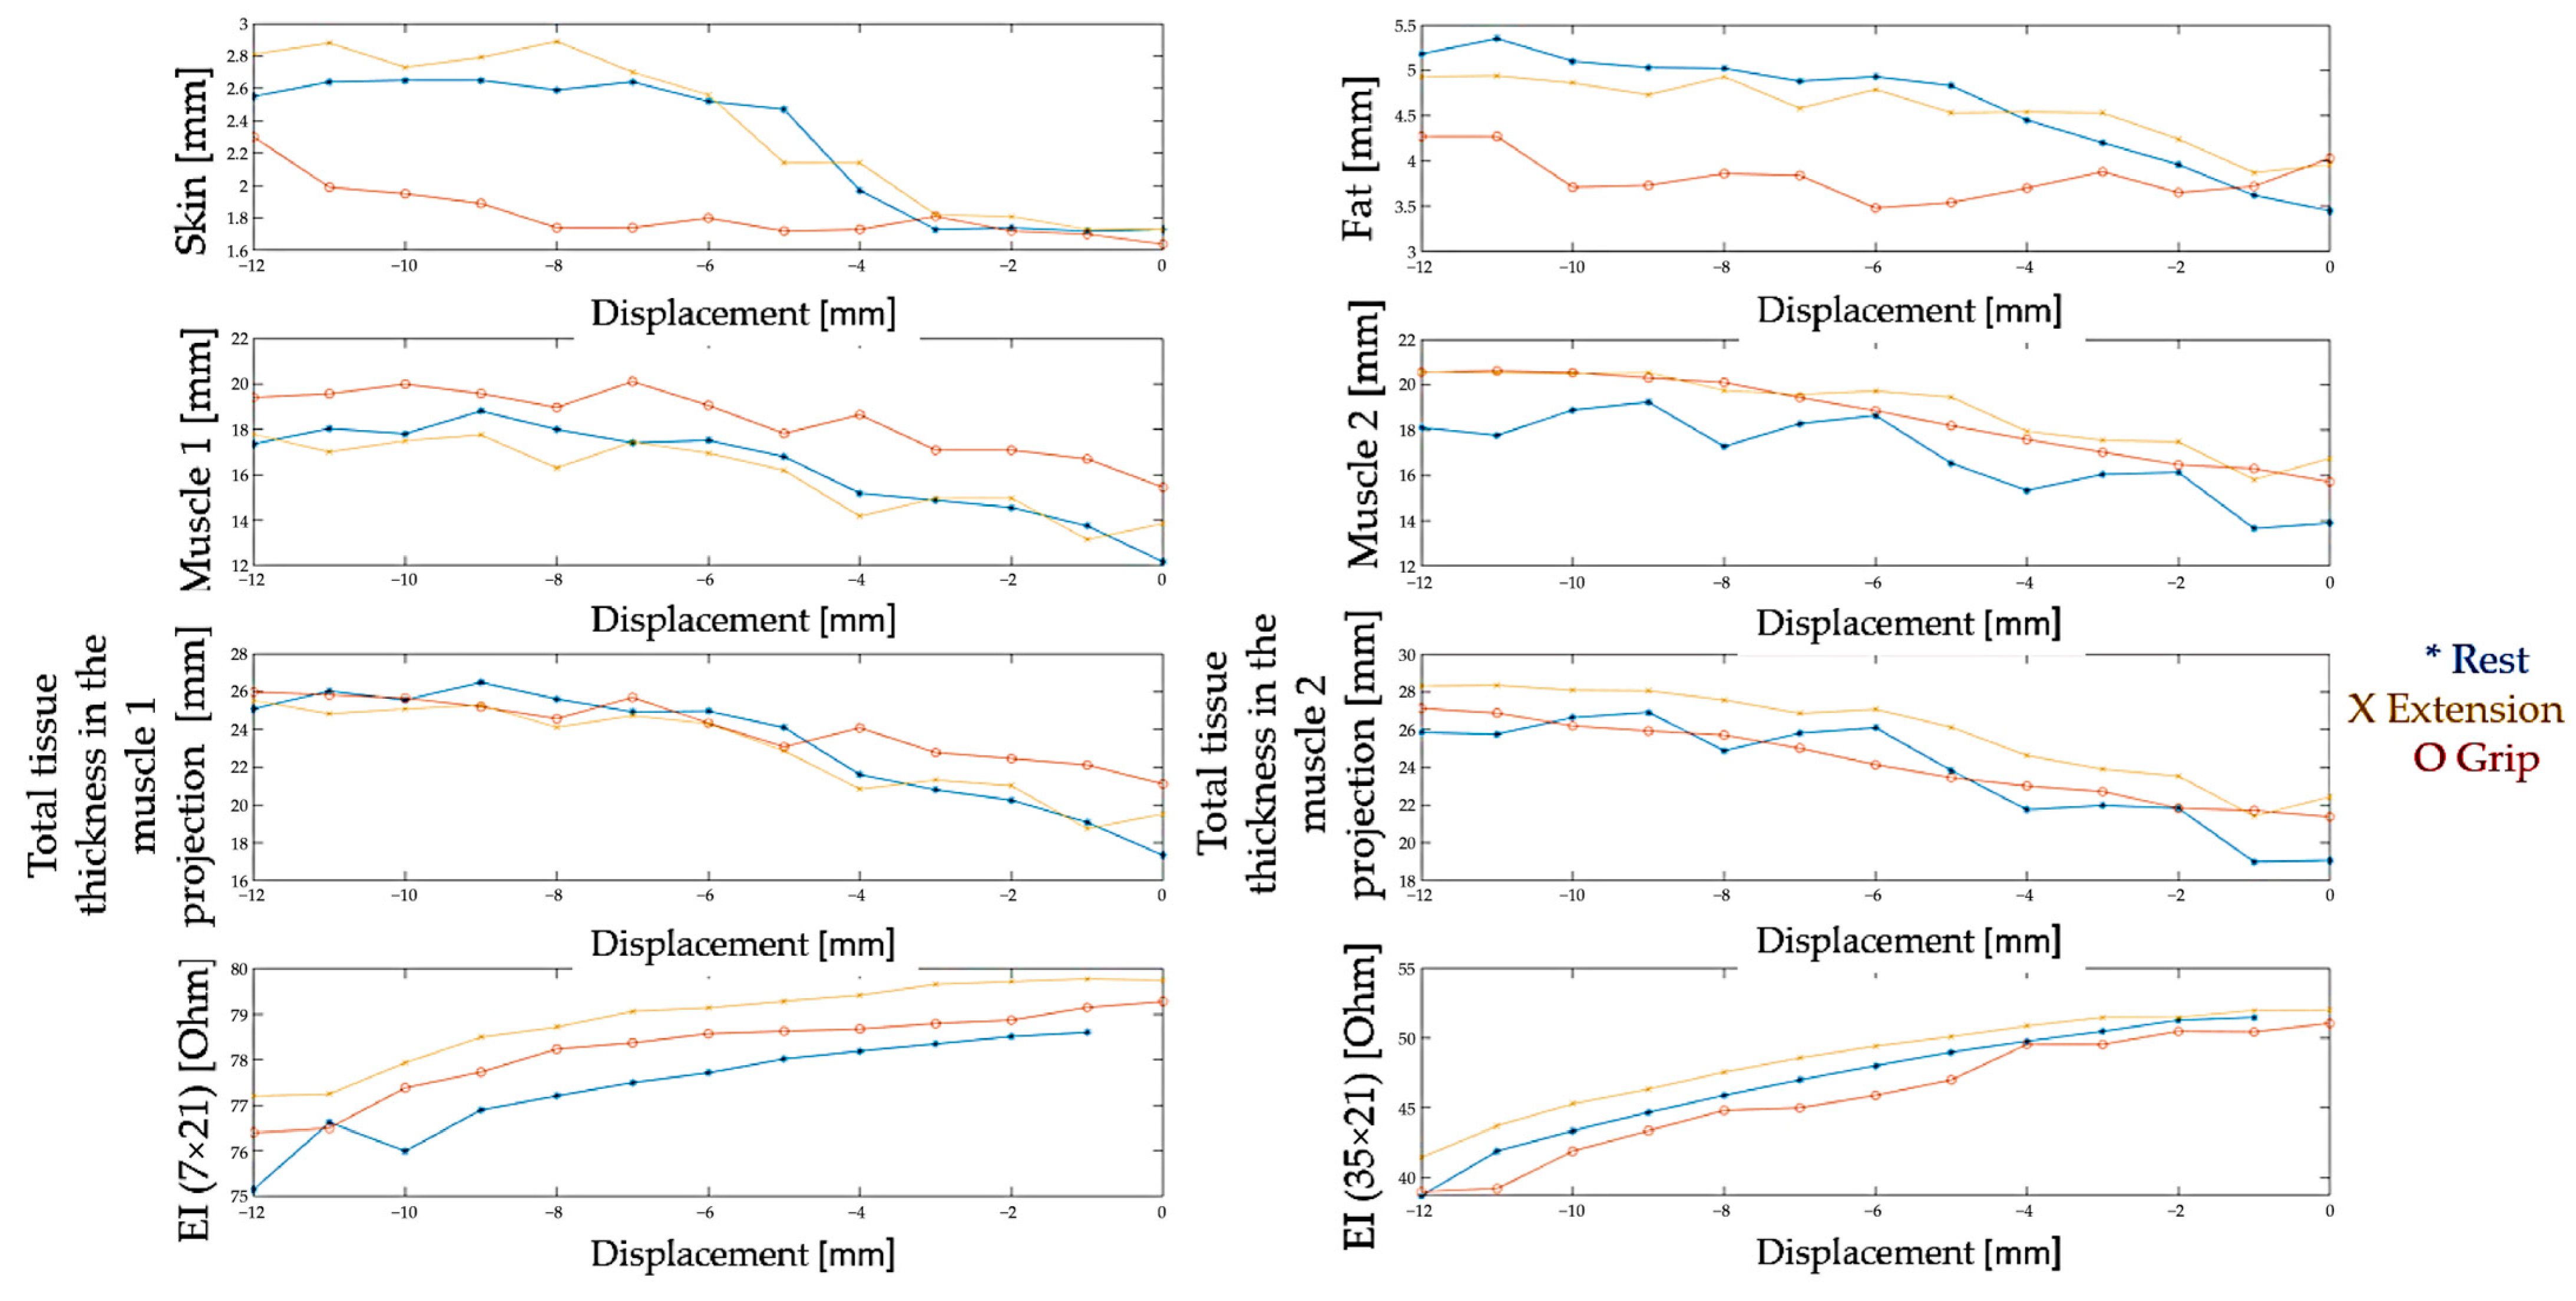

3.1. Study of Morphofunctional Activity of the Forearm Muscles When Performing Actions

3.2. Study of the Amplitude Parameters of the Electrical Impedance Myography Signal at Different Pressures of the Electrode System